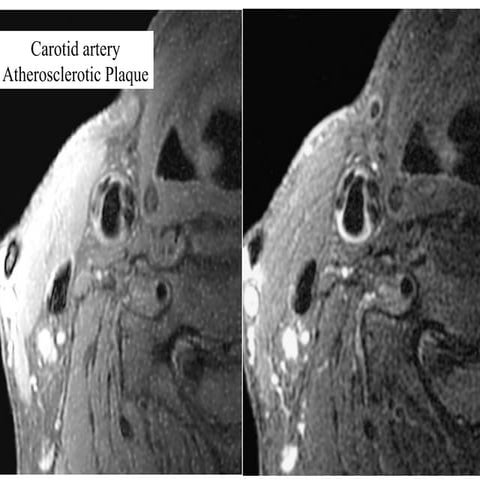

The First High Resolution CarotidThe First High Resolution Carotid

ImagingImaging by a 3T MRIby a 3T MRI

The First HighResolution CarotidThe First High Resolution Carotid ImagingImaging by a 3T MRIby a 3T MRI Fine structures like plaque cap now can be imaged. May 2003

1.5 T; 2NEX; resolution 0.63x0.63 mm 3 T; 2 NEX; resolution 0.63x0.63 mm 3 T; 1 NEX; resolution 0.27x0.55 mm1.5 T; 1 NEX; resolution 0.27x0.55 mm Comparing 1.5 and 3TComparing 1.5 and 3T without Software Enhancementwithout Software Enhancement GE 3T and 1.5T Scanners with Identical Phased-array Design